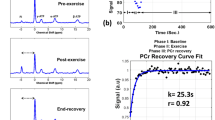

The calves of seven healthy subjects underwent imaging pre- and post-exercise via 7 T 23Na MRI (3D fast low angle shot, TR/TE = 80 ms/0.160 ms, 4 mm × 4 mm × 4 mm) and 1 week later by 1H MRI (multiple spin-echo sequence, TR/TE = 3,000 ms/15–90 ms). Four type 2 diabetics also participated in the 23Na MRI protocol. Pre- and post-exercise sodium signal intensity (SI) and proton T2 relaxation values were measured/calculated for soleus (S), gastrocnemius (G), and a control, tibialis anterior (TA). Two-tailed t tests were performed.

In S/G in healthy subjects post-exercise, sodium SI increased 8–13% (p < 0.03), then decreased (t 1/2 = 22 min), and 1H T2 values increased 12–17% (p < 0.03), then decreased (t 1/2 = 12–15 min). In TA, no significant changes in sodium SI or 1H T2 values were seen (−2.4 to 1%, p > 0.17). In S/G in diabetics, sodium SI increased 10–11% (p < 0.04), then decreased (t 1/2 = 27–37 min) without significant change in the TA SI (−3.6%, p = 0.066).

It is feasible to evaluate skeletal muscle via 3D 23Na MRI at 7 T. Post-exercise muscle 1H T2 values return to baseline more rapidly than sodium SI. Diabetics may demonstrate delayed muscle sodium SI recovery compared with healthy subjects.